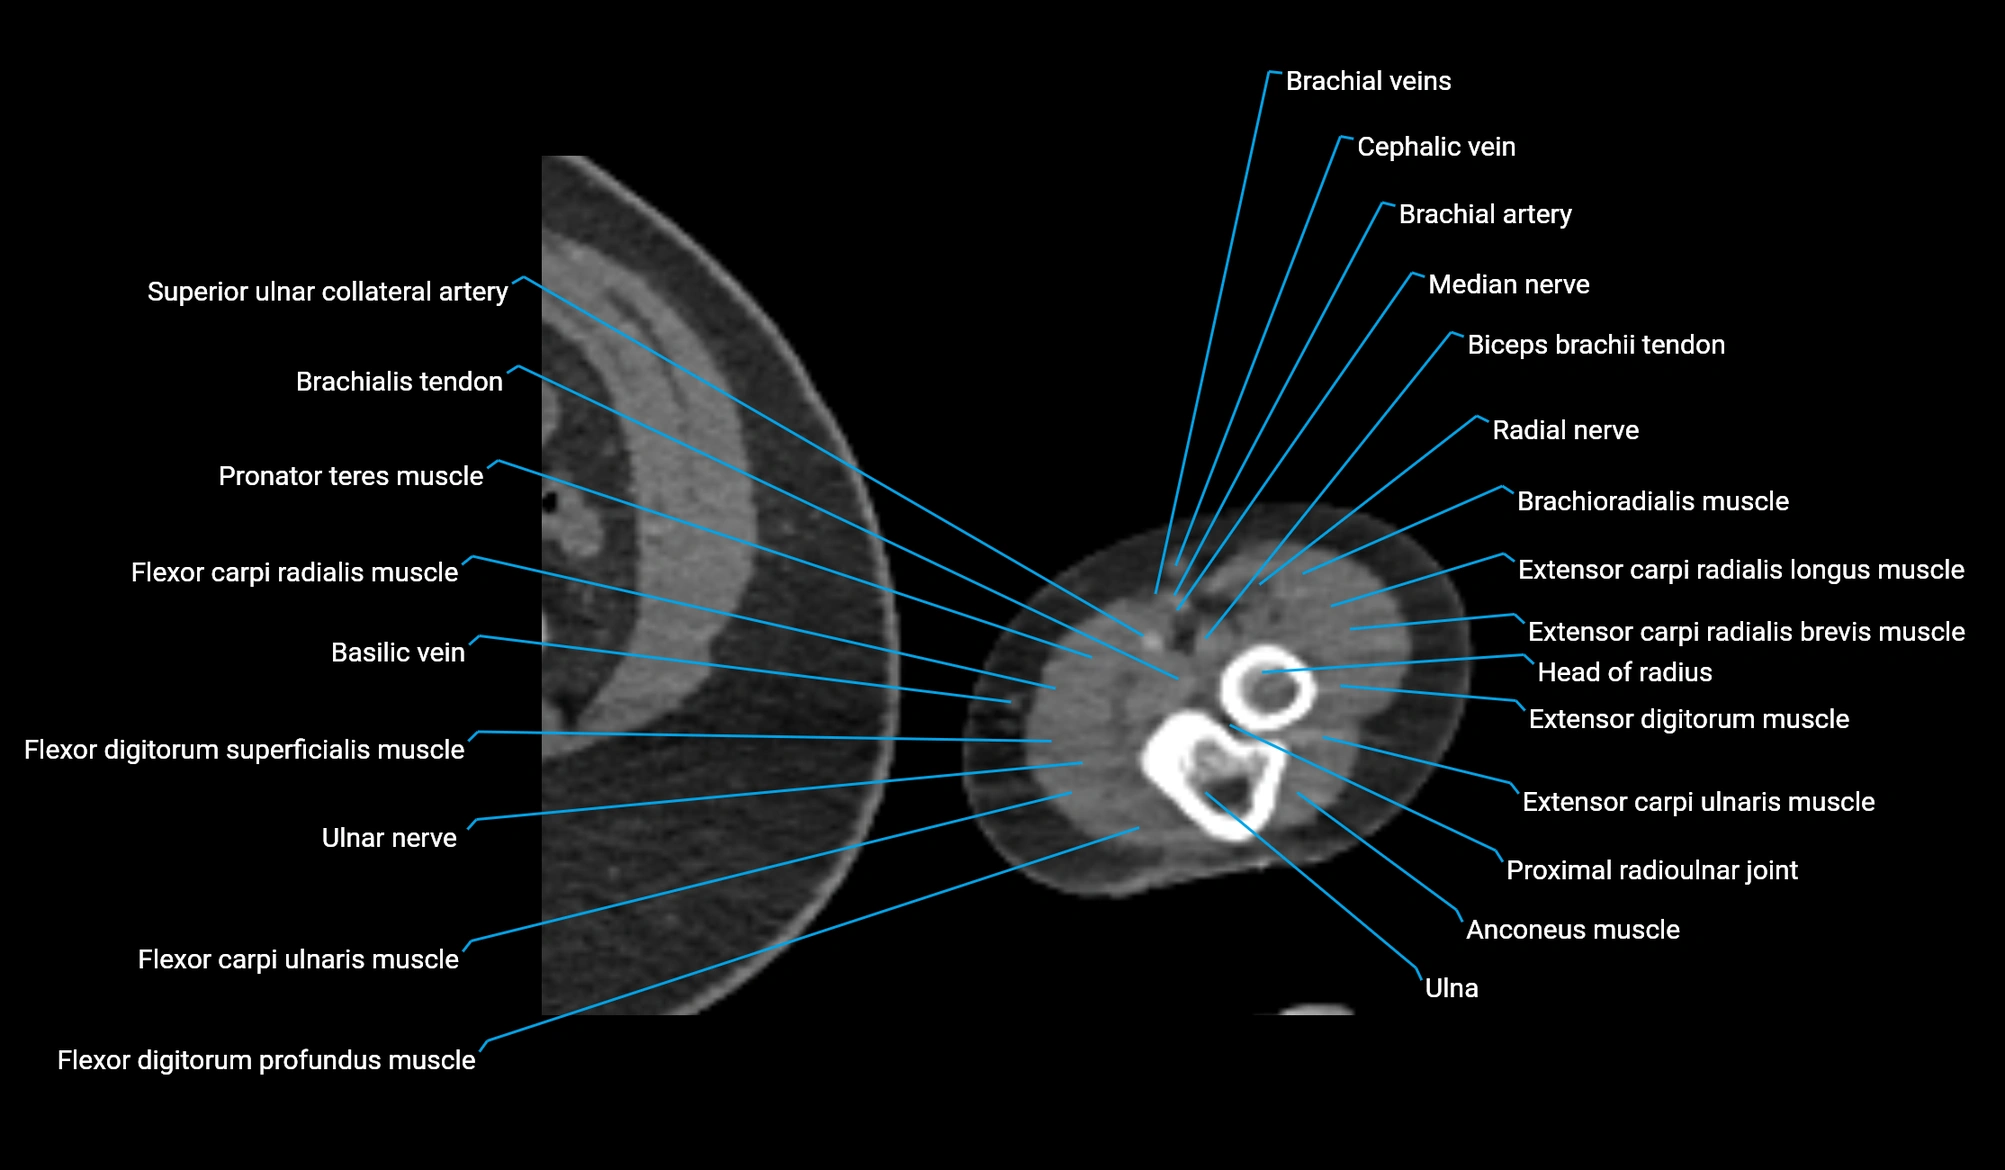

- Basilic vein

- Brachial artery

- Cephalic vein

- Extensor carpi radialis brevis muscle

- Extensor carpi radialis longus muscle

- Extensor carpi ulnaris muscle

- Extensor digitorum muscle

- Flexor carpi radialis muscle

- Flexor carpi ulnaris muscle

- Flexor digitorum profundus muscle

- Flexor digitorum superficialis muscle

- Head of radius

- Median nerve

- Pronator teres muscle

- Proximal radioulnar joint

- Radial nerve

- Radial recurrent artery

- Superior ulnar collateral artery

- Ulna

- Ulnar nerve